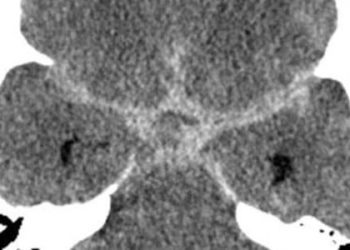

Image: CC Sasha Wolf, wikipedia